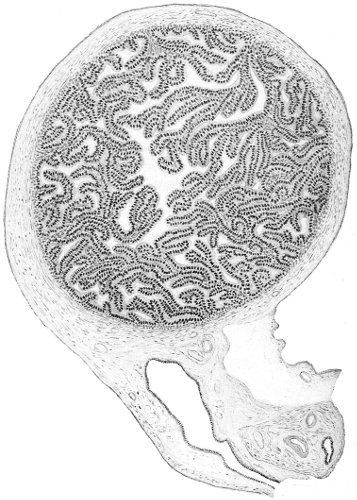

An accurate knowledge of the anatomy and mechanism of the female perineum is essential to an understanding of the nature and treatment of injuries to this structure. The anatomical structures lying between the anus behind and the symphysis pubis in front are those that most directly interest the gynecologist. Proceeding from 57 below upward, we find the following structures lying in superimposed planes: the skin, the superficial fascia, the deep layer of the superficial fascia, the transversus perinæi and the sphincter vaginæ muscles, the anterior layer of the triangular ligament, the posterior layer of the triangular ligament, the levator ani muscle (Fig. 19).

The vagina passes through these structures. They surround and support the ostium vaginæ as the fascia and muscles surround and support the opening of the rectum or the anus. The muscles and fasciæ are attached in the median line between the anus and the vagina, and therefore this part of the body, which is called the perineum, is supported or maintained in its 58 proper position by these various structures. The transversus perinæi arises from the ramus of the ischium and is inserted in the perineum. The bulbo-cavernosus, or sphincter vaginæ, arises in the perineum and is inserted in and about the clitoris. The inner fibers of the levator ani arise from the symphysis pubis and are inserted in the perineum and the lower part of the vagina (Fig. 20). When these muscles contract, their action, therefore, is to draw the perineum upward and forward. At the same time the anus is drawn upward and forward, and so also is the posterior margin of the ostium vaginæ and the lower portion of the posterior vaginal wall.

The vagina has no circular sphincter like the anus, but 59 the vaginal month is kept closed by the action of the transversus perinæi, sphincter vaginæ, and levator ani muscles, which draw the perineum forward, and thus keep the posterior vaginal wall in apposition with the anterior wall.

Fig. 21.—Muscular floor of the pelvis seen from above.

This sling of muscles and fascia, which surrounds and supports the opening of the vagina, may readily be felt in the nulliparous woman by introducing the finger in the vagina and pressing backward and outward toward the ischio-rectal fossa. We then feel plainly, immediately within the ostium vaginæ, a firm resisting band of tissue, apparently about half an inch broad, embracing the posterior portion of the lower vagina. This band is formed by the inner edges of the various muscles and planes of fascia that have been described.